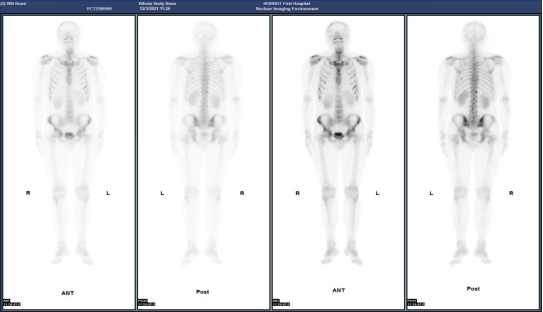

(病例二)患者,男,63岁,患者因胸憋气短、间断咳嗽咳痰就诊。门诊CT示:双肺底感染;右肺上叶占位性病变。患者今年4月份提重物时感右侧胸部拉伤,后疼痛数日。MIP图示:C6/C7椎体吻合面、右侧第7侧肋小片状放射性摄取增高,SPECT/CT示:右侧第7侧肋骨质不连续,可见骨痂形成。C6/C7椎体吻合面可见唇样骨质增生,椎体周围软组织无明显肿胀。结合病史,考虑右侧第7侧肋骨折愈合期;C6/C7椎体吻合面终板炎。